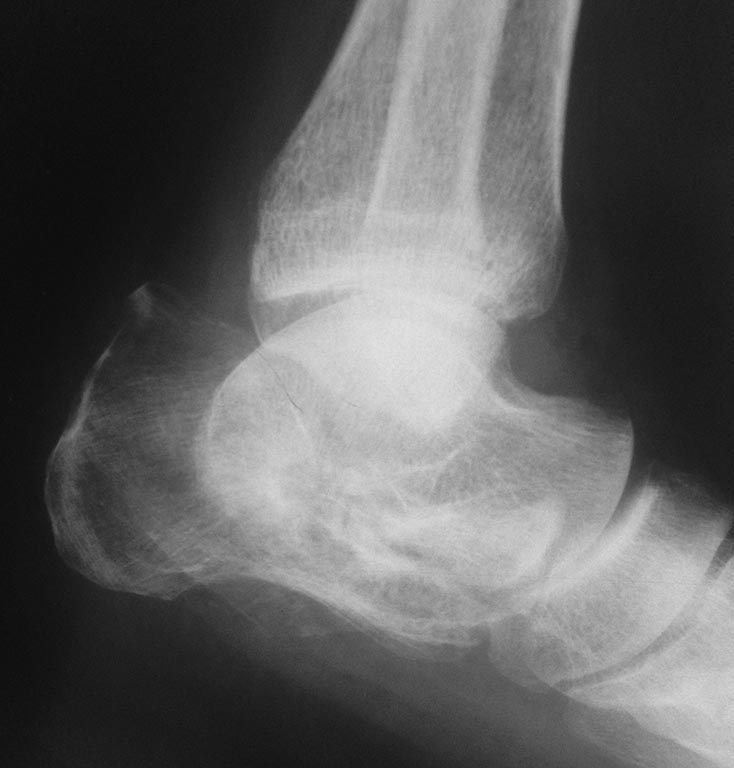

Судя по снимку, пятка срослась и анкилоз в подтаранном суставе состоялся. Про жалобы и локальный статус Вы ничего не пишете. А если ориентироваться только на снимок, то со стопой делать сейчас ничего не нужно. Когда начнет наступать на нее можно будет подобрать комфортную (ортопедическую?) обувь и, вероятно, индивидуальную стельку. Или подпяточник. А на голени перелом позволяет применить любой способ фиксации на Ваше усмотрение. Опять же, с учетом локального статуса (качество кожного покрова, гнется ли колено и т.д.)

Там еще мыщелок медиальный сломан... А по стопе неплохо бы КТ. Лучше бы с 3D моделированием.

Полагаю,необходимо проводить коррегирующий пяточно - таранный артродез для восстановления пяточно - таранных взаимоотношений, в случае, если позволяет состояние мягких тканей. В случае с голенью целесообразен БИОС пластиной с подъёмом импренированной части мыщелка.

Всем добрый день. я предлагаю провести КТ голени, возможно с методом фиксации что-то измениться.